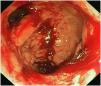

Varón de 27 años, con antecedentes familiares de madre y hermanas portadoras sanas de enfermedad granulomatosa crónica, diagnosticado de la misma entidad a los 18 meses. A los 19 años, presentó un cuadro de intensa diarrea sanguinolenta con grave afectación del estado general, que llevó a la realización de un colectomía subtotal e ileostomía de descarga, con cierre posterior de ésta y anastomosis término-terminal. El diagnóstico anatomopatológico de la pieza quirúrgica fue de colitis crónica granulomatosa y ulcerosa, con afectación del apéndice e íleon terminal. Actualmente, el paciente se encuentra en tratamiento con cotrimoxazol e itraconzaol, así como mesalazina (5 ASA), y presenta una tendencia a infecciones respiratorias de repetición, así como un número de 4-5 deposiciones diarias. Se realiza colonoscopias de forma programada (fig. 1), así como controles analíticos e inmunológicos para seguir de forma atenta su comportamiento.

Estos pacientes también presentan complicaciones inflamatorias no infecciosas, entre las cuales la afectación intestinal es de las más frecuentes, especialmente en la forma ligada a X3. Su patogenia se desconoce, pero parece que la estimulación antigénica de los organismos, que no han podido ser destruidos por los fagotitos, conllevan la formación de granulomas y al engrosamiento de la pared intestinal. La apariencia endoscópica en la EGC recuerda a la enfermedad inflamatoria intestinal, ya que también cursa con friabilidad mucosa, hemorragias petequiales e incluso formación de seudopólipos o seudomembranas4. Sin embargo, difieren histológicamente. Así, en la EGC encontramos un aumento de infiltrado de eosinófilos y macrófagos pigmentados, con ausencia de neutrófilos. La expresión de HLA-DR y de moléculas de adhesión está incrementada en el epitelio y en el endotelio vascular, lo cual favorece la llegada de esosinófilos, pero no de neutrófilos5.